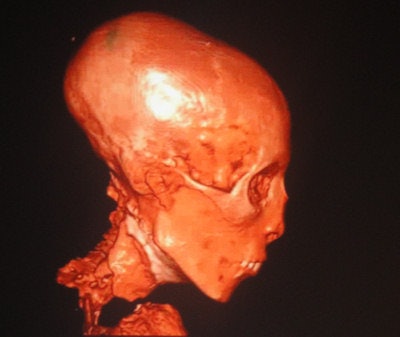

"These people really knew their anatomy," he told ICR delegates of the ancient Egyptians who performed the mummification. "The first step in mummification was to introduce an iron rod in one of the nostrils, breaking the cribriform plate of the ethmoid bone, which is the thinnest part of the skull base, so they could extract all the brain out of the nostrils, and then they poured in the embalming material."

Because the organs were full of water and would putrefy, the ancient Egyptians removed them and stored them in canopic jars put next to the mummies' bodies. This was done to ensure that the mummies would enter the afterlife, Selim explained. They removed all organs except the heart, because they were convinced the soul returned via the heart.

Complete dehydration was essential to achieve successful mummification, he added. The ancient Egyptians did that by packing the body with linen bandages soaked in natural salt, which imbibed water from the tissues, and they also added ointments to make sure the body smelt pleasant. Then they left the body to dry out for between 40 days and 70 days, which is why some Arab cultures still celebrate the 40th day after a death has occurred.